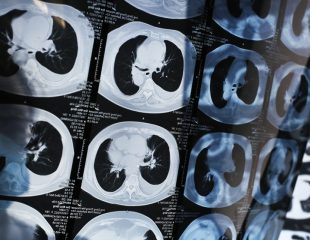

مرحله چهارم سرطان ریه GAME OVER!

مرحله چهارم سرطان ریه پیشرفتهترین مرحله این بیماری است. در مرحله 4، سرطان به هر دو ریه، ناحیه اطراف ریهها ...

آنچه در مرحله 3 سرطان ریه به سر مبتلایان میآید

سرطان ریه عامل اصلی مرگ و میر ناشی ازانواع سرطان ها در ایالات متحده است. به گفته مرکز پیشگیری و ...